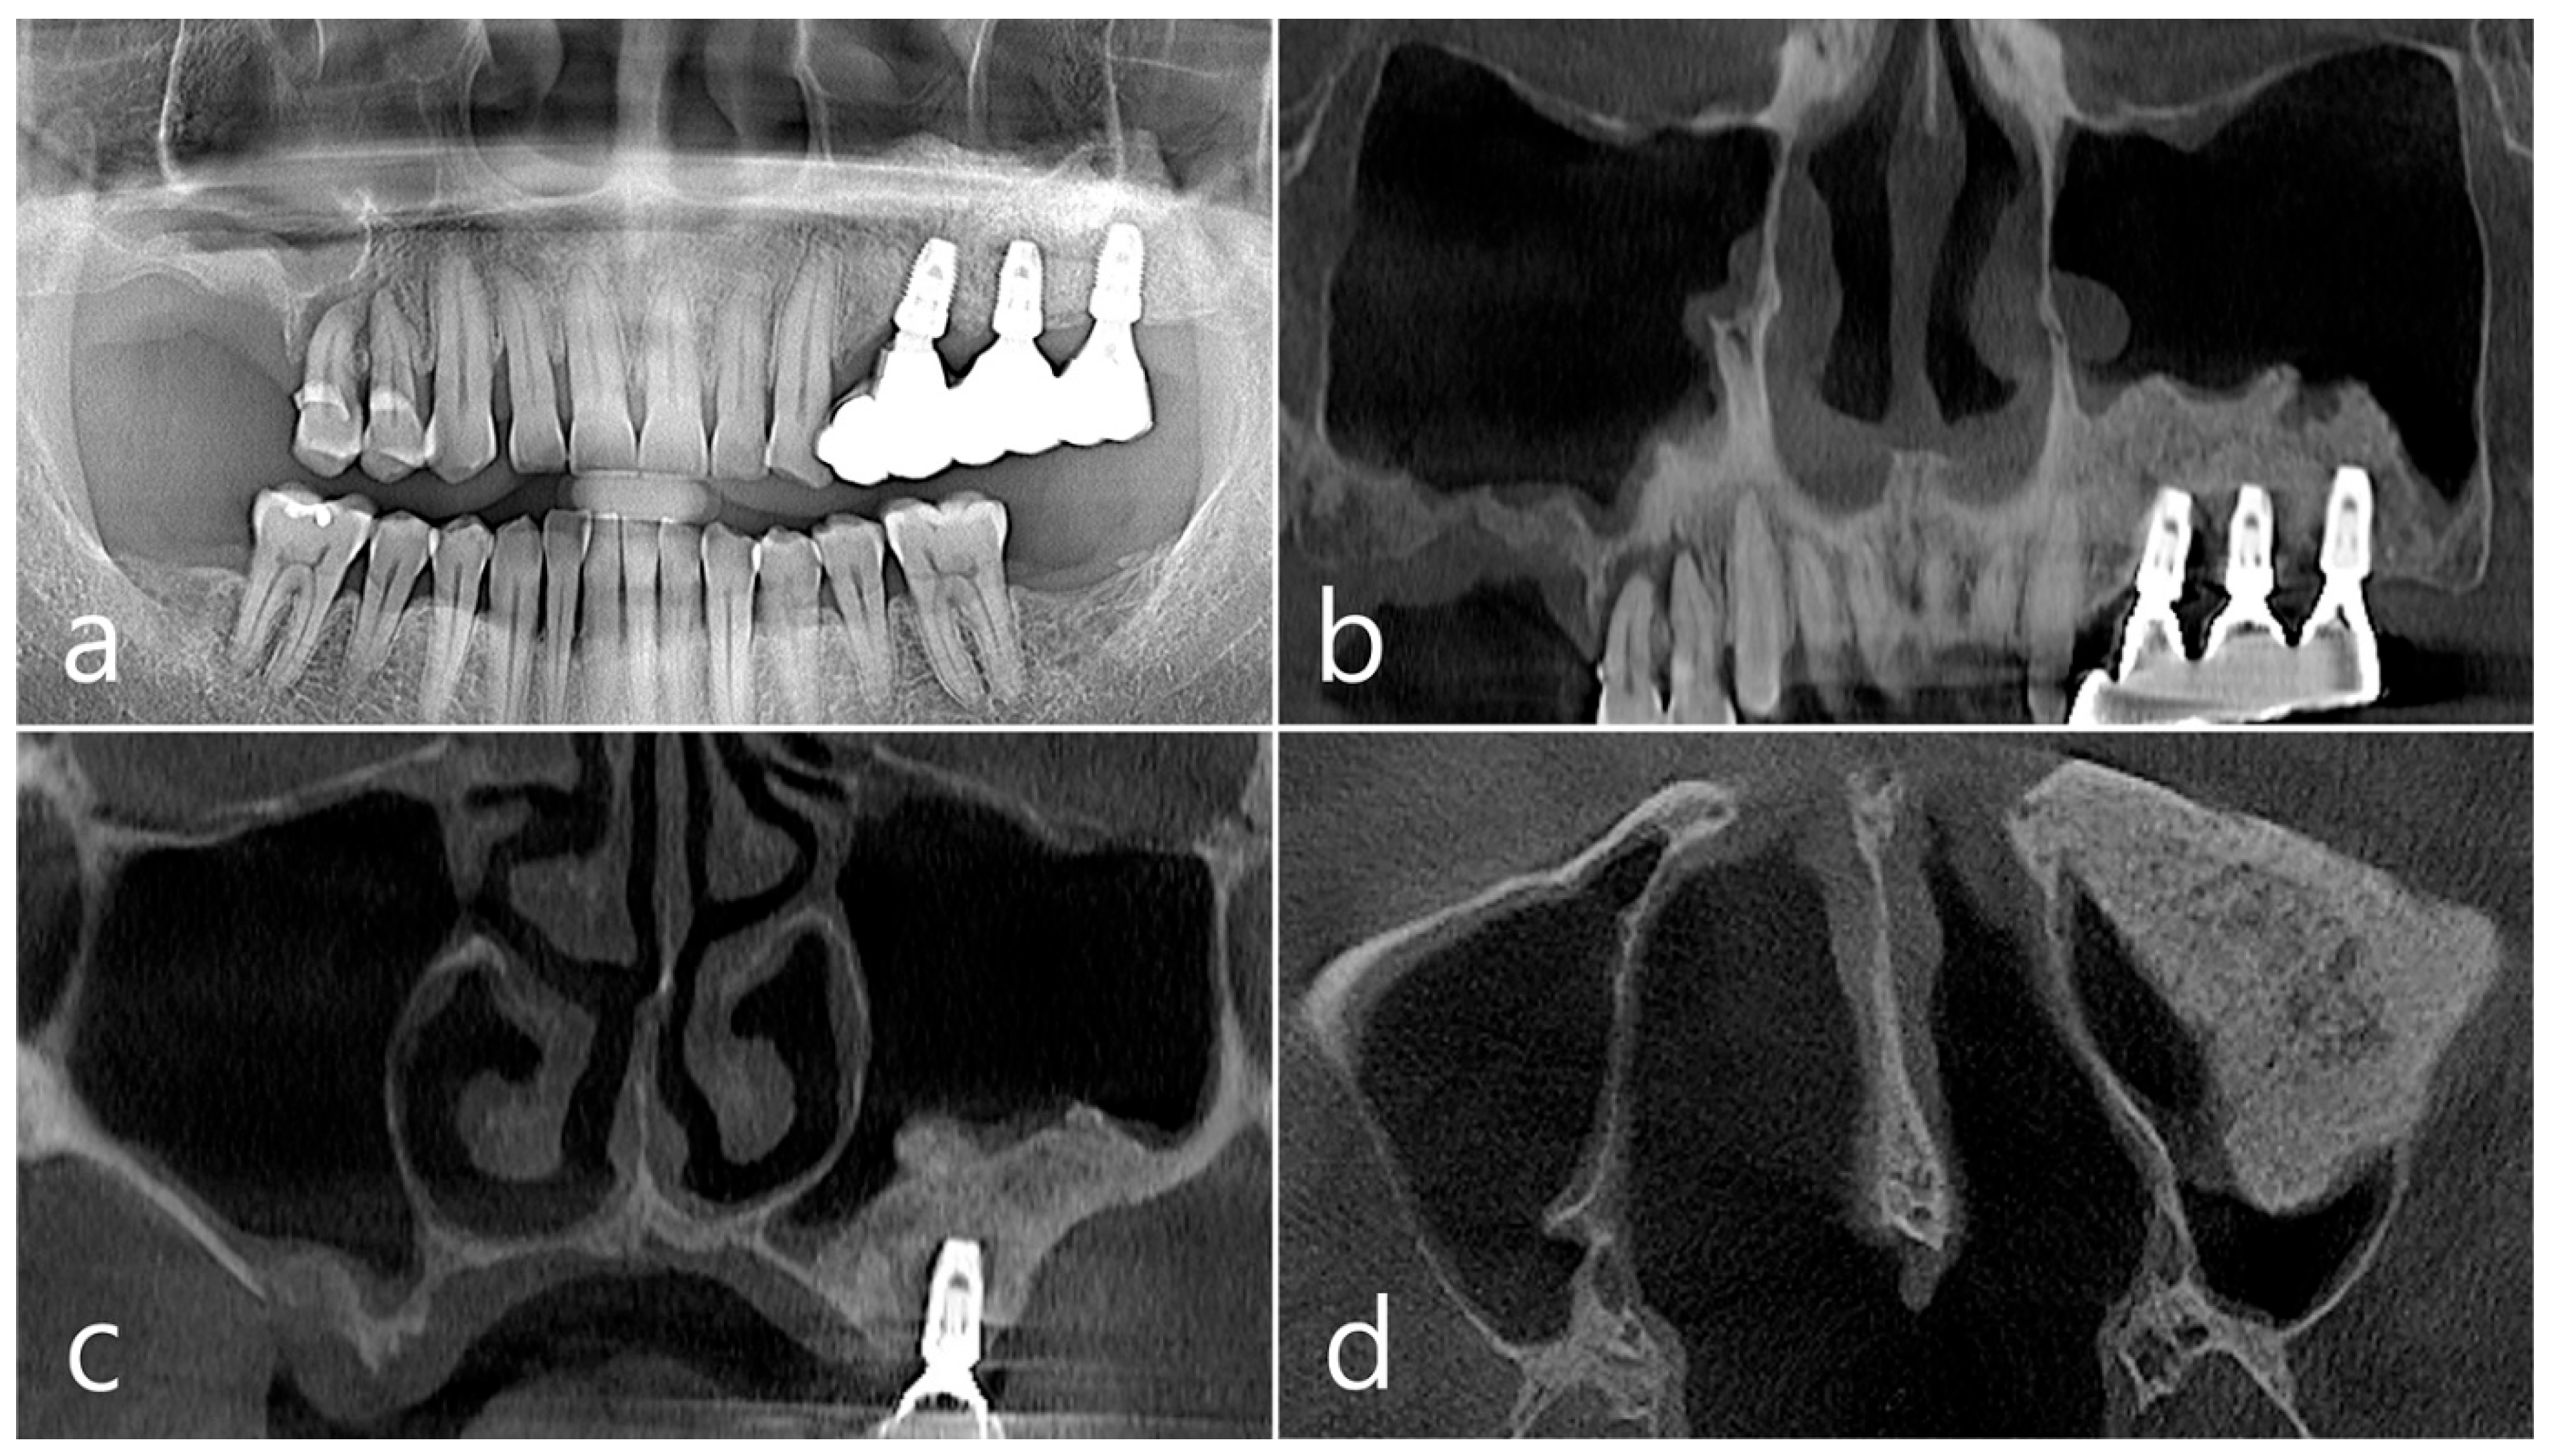

2.2. Case 2

This patient was a 58-year-old male smoker who was taking antihypertensive drugs. The patient visited our clinic for implant placement in the upper left posterior region. Teeth #24 and #25 were determined to be extracted due to severe periodontal disease. In panoramic radiography, the residual alveolar bone was severely atrophied, and pneumatization of the maxillary sinus was severe (Figure 7a). In CBCT imaging, membrane thickening was observed in the sinus floor, but there was no membrane thickening in the rest of the sinus wall (Figure 7b–d).

Figure 7. Case 2. (a,b) On the preoperative panoramic radiography and panoramic image of CBCT, the residual alveolar ridge in the posterior maxilla was severely atrophied and pneumatization of maxillary sinus was severe; (c,d) In CBCT imaging, mucosal thickening (arrows) ranging from 2 to 15 mm was observed in the sinus floor, depending on the location, but there was no mucosal thickening in the rest of the sinus wall.